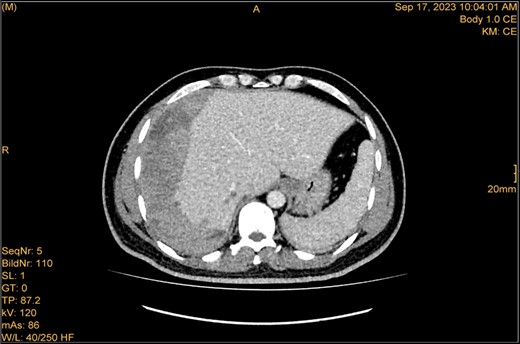

A 41-year-old male with a clear medical background, presented to the Emergency Department with right upper quadrant (RUQ) abdominal pain for two days, associated with fatty dyspepsia, anorexia, nausea, and vomiting. On arrival, his heart rate was 111 bpm with a blood pressure of 128/94 mmHg. On examination, a yellowish discoloration of skin and sclera was noted with a negative murphy sign. Investigations showed elevated liver enzymes (LFT). An initial abdominal ultrasound showed a distended gallbladder with a thickened wall and multiple stones, largest measuring approximately 1.4 cm, and a common bile duct measuring 5 mm (Fig. 1). A magnetic resonance cholangiopancreatography (MRCP) identified a tiny 4-mm mid-cystic duct stone without intrahepatic biliary dilatation. After the initial management, an emergency LC was performed, which posed minimal challenges. Fortunately, no intraoperative complications were reported. A drain was kept in the subhepatic area, and the patient was kept under close observation. Second day postoperatively, the patient experienced dizziness and an intense RUQ pain despite proper analgesia. His heart rate was 89 bpm with a blood pressure of 107/64 mmHg. Investigations showed a drop in hemoglobin level from 13.8 to 9.9 g/dl. An abdominal ultrasound showed a right subcapsular heterogeneous collection with a scalloped liver surface (Fig. 2). Therefore, an initial diagnosis of ISH post-LC was considered. Following the initial fluid resuscitation and blood transfusion, a further decline in hemoglobin level was noted reaching 8.8 g/dl. Further blood transfusion was commenced achieving stabilization. Further CT scan showed subcapsular hepatic hematoma measuring 7.1 × 19 × 21 cm, in its transverse, anteroposterior, and craniocaudal diameters, respectively, with no evidence of active extravasation (Fig. 3) confirming the final diagnosis of ISH post-LC. A multidisciplinary decision was made to continue conservative management after a proper explanation of the potential risk of sudden rupture of hematoma. The patient’s clinical condition and hemoglobin level, in addition to drain output, were meticulously monitored in the general ward, ensuring early detection of deterioration. Four days later, a follow-up CT scan revealed no new significant interval changes (Fig. 4). Nine days postoperatively, the patient was discharged with a follow-up appointment, which showed almost complete resolution.

The study was done utilizing monophasic porto venous phase demonstrating intact vasculature. Relatively stable significant subcapsular and intraparenchymal hepatic hematoma with underlying parenchymal contusion and laceration. The study appears unremarkable with no new significant interval change.